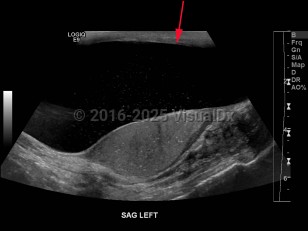

Hydrocele of testis

A hydrocele is an accumulation of serous fluid between the visceral and parietal layers of the tunica vaginalis, which covers the testes and spermatic cord. Hydroceles may be communicating or noncommunicating. A communicating hydrocele results from failure of closure of the tunica vaginalis leaving a patent process. This is most common in newborns. The fluid is often reducible. Noncommunicating hydroceles have no connection to the peritoneal cavity and are not reducible.

A hydrocele often presents as a painless visible or palpable cystic mass in the scrotum and otherwise is usually asymptomatic.